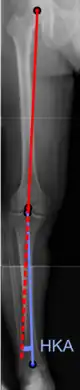

On projectional radiography, the degree of varus or valgus deformity can be quantified by the hip-knee-ankle angle,[7] which is an angle between the femoral mechanical axis and the center of the ankle joint.[8] It is normally between 1.0° and 1.5° of varus in adults.[9] Normal ranges are different in children.[10]

Hip-knee-ankle angle.